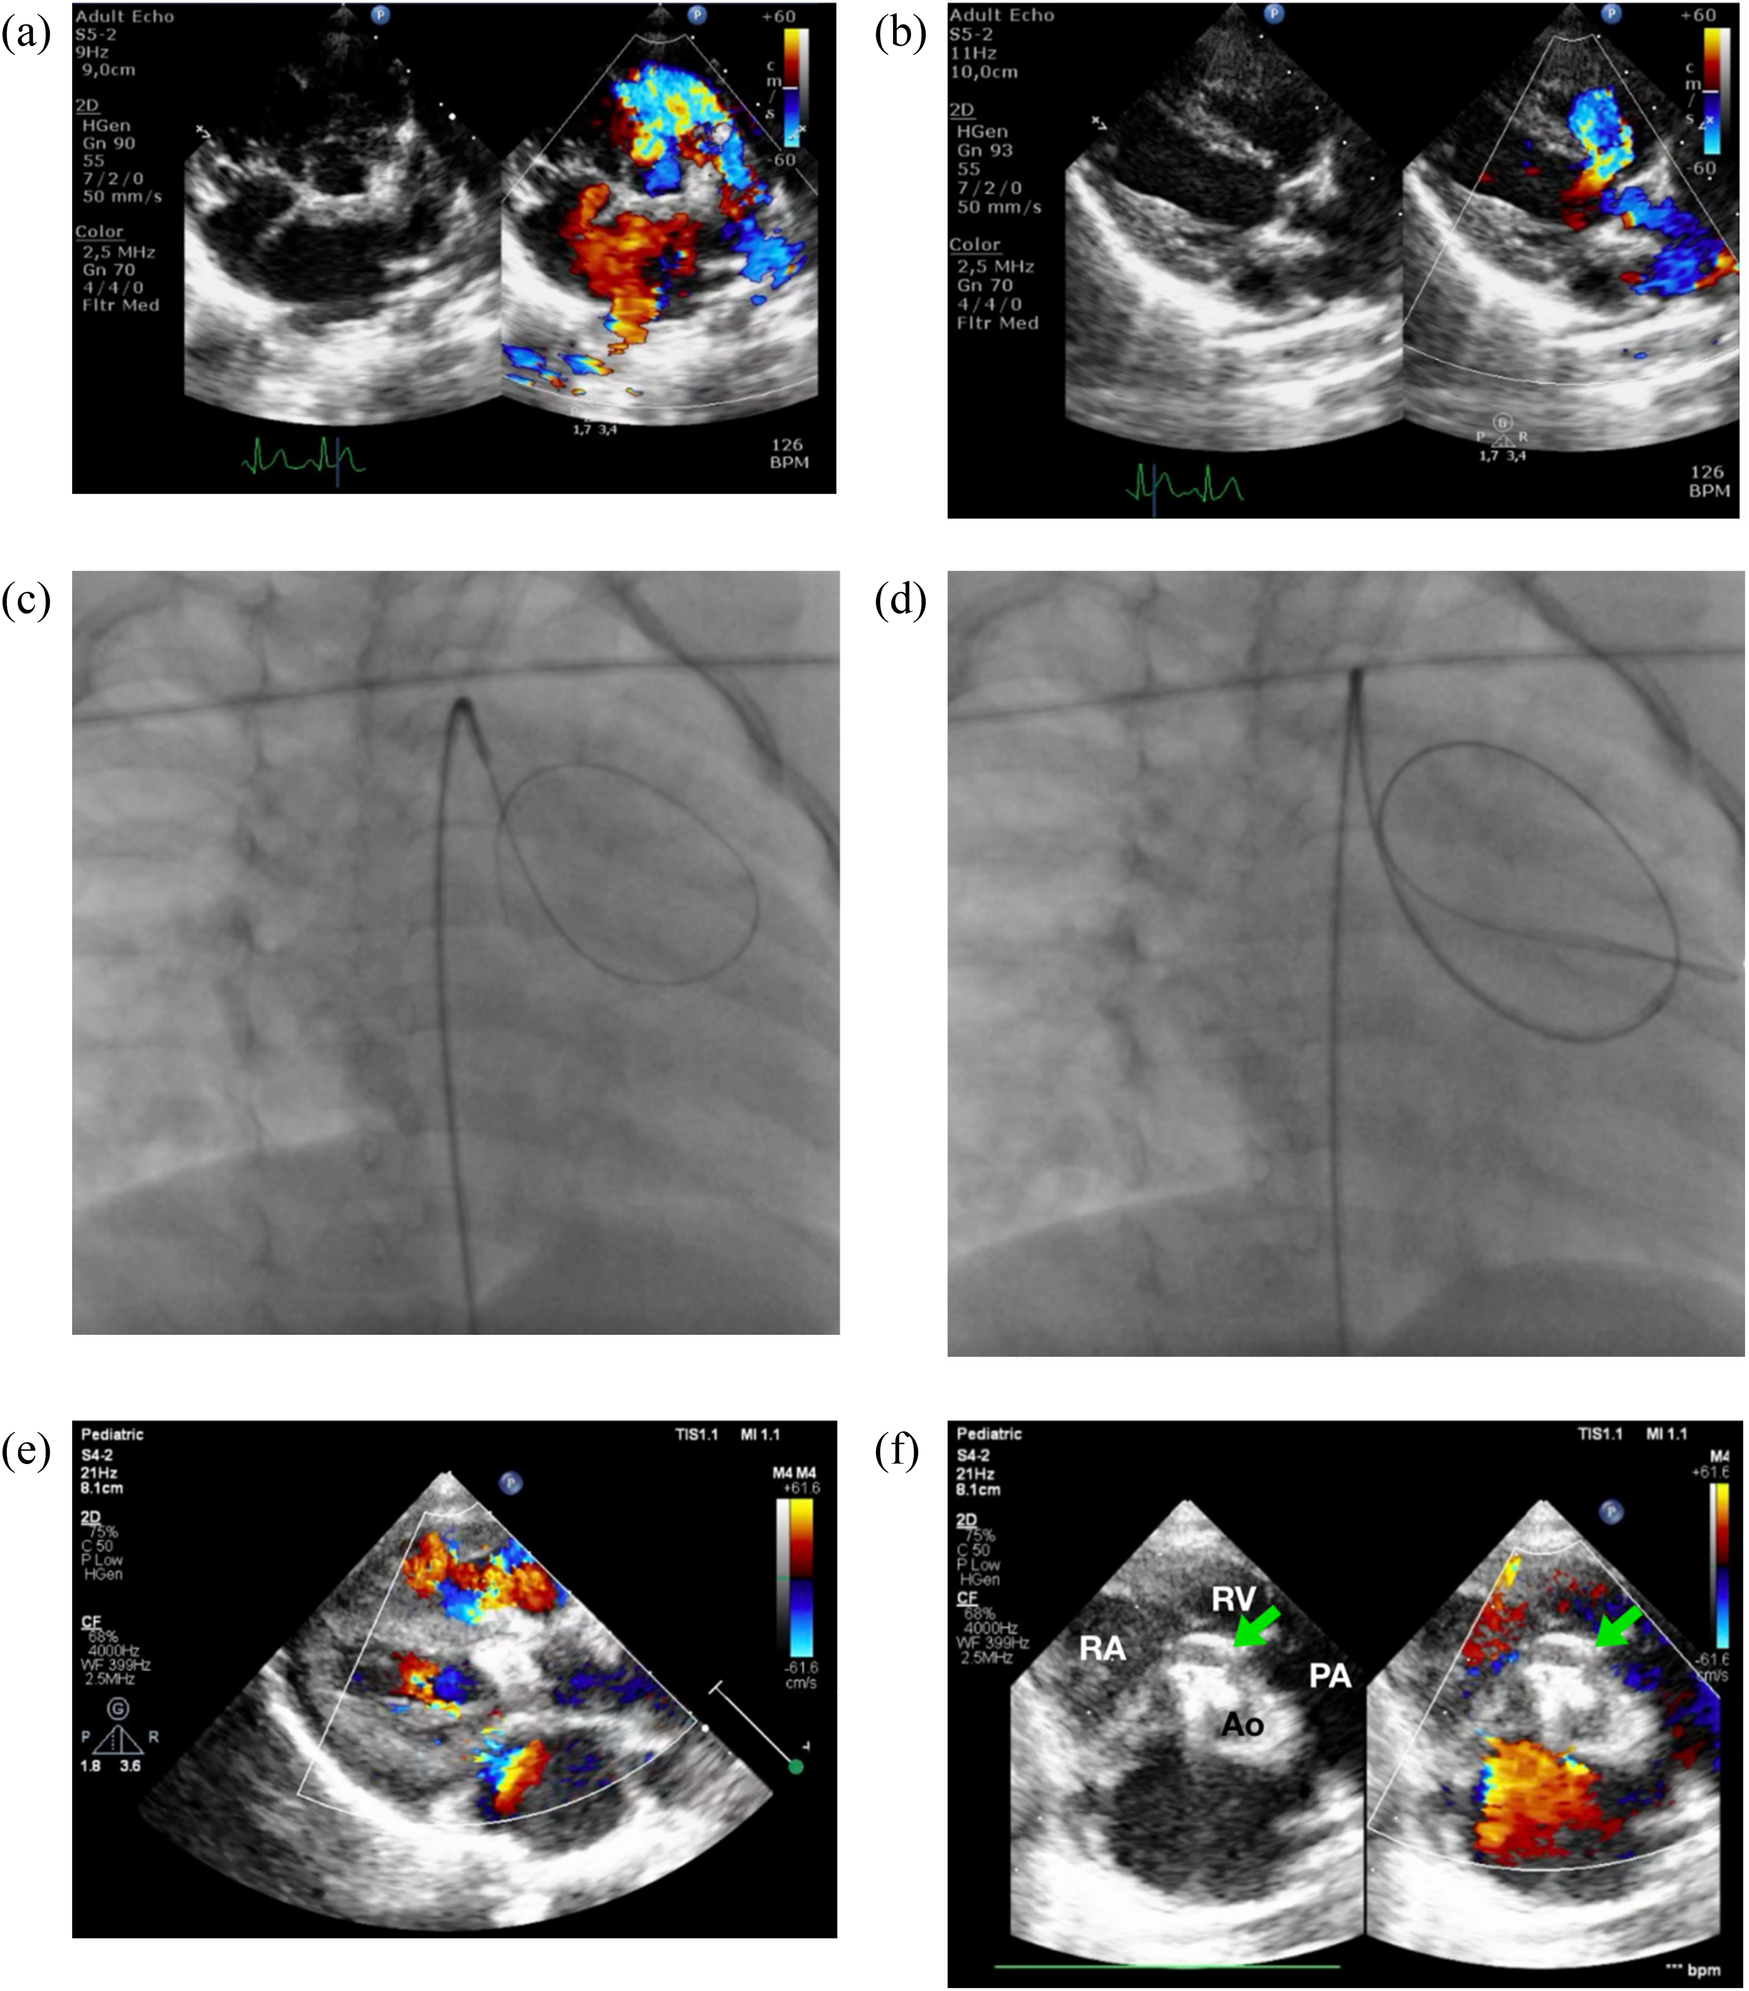

Figure 1

Zero-contrast closure of a doubly-committed subarterial VSD. Transthoracic echocardiography revealed a DCSA VSD in both the parasternal short-axis/PSAX (a) and long-axis/PLAX (b) views. Simultaneous fluoroscopy with the view of RAO 30/CRAN 0 (c,d) and transthoracic echocardiography was employed to cross the VSD by using 3.5/5F JR guiding catheter and 0.035″ soft hydrophilic exchange wire. Following device deployment, imaging confirmed proper device placement without evidence of aortic or tricuspid regurgitation (e). (f) PSAX view at aortic level confirmed device edge is touching the pulmonary valve, but no aortic regurgitation was observed. RA, right atrium; RV, right ventricle; PA, pulmonary artery; Ao, aorta.

The patient was sedated, and antiseptic preparation was performed on the left and right inguinal regions. A puncture was made in the right femoral artery, and a 5F sheath was inserted. Following this, 900 IU of intra-arterial heparin was administered, and a 3.5/5F JR guiding catheter was advanced through the right femoral artery, descending aorta, aortic arch, and ascending aorta into the left ventricle. Cefuroxime 450 mg was administered intravenously for prophylaxis. An attempt was made to cross the ventricular septal defect (VSD) from the left ventricle (LV) to the right ventricle (RV) using the 3.5/5F JR guiding catheter assisted by a 0.035″ soft hydrophilic exchange wire, but this was unsuccessful. The catheter was then switched to a 5F left internal mammary (LIMA) catheter and a 3.5/4F JR diagnostic catheter, also guided by a soft hydrophilic wire, but the attempts remained unsuccessful. The operator decided to proceed with fluoroscopic guidance, still without the use of contrast. A 3.5/5F JR guiding catheter was reintroduced via the right femoral artery, advanced through the descending aorta, aortic arch, and ascending aorta. Guided by the 0.035″ soft hydrophilic exchange wire, the catheter successfully crossed the VSD from the LV to the RV (Figures 1c,d), with the wire anchored in the pulmonary artery, still with zero contrast technique. A Konar-MF VSD occluder (size 7/5 mm) was deployed through the 3.5/5F JR guiding catheter. The high-pressure disc was positioned in the RV and retracted to seal the VSD, while the low-pressure disc was deployed within the LV to complete the occlusion.

Post-procedural transthoracic echocardiography (TTE) revealed a preserved left ventricular ejection fraction (EF) of 69% (Teichholz) and good right ventricular (RV) contraction. The device was securely positioned, with no residual VSD detected through the device (Figures 1e,f). The cardiac valves were intact, with no evidence of tricuspid regurgitation or aortic regurgitation. A tug test confirmed the stability of the device. The total fluoroscopy time was 3.1 min, with a dose area product (DAP) of 40 mGy. At the most recent follow-up, the patient was asymptomatic, with no reported complications.